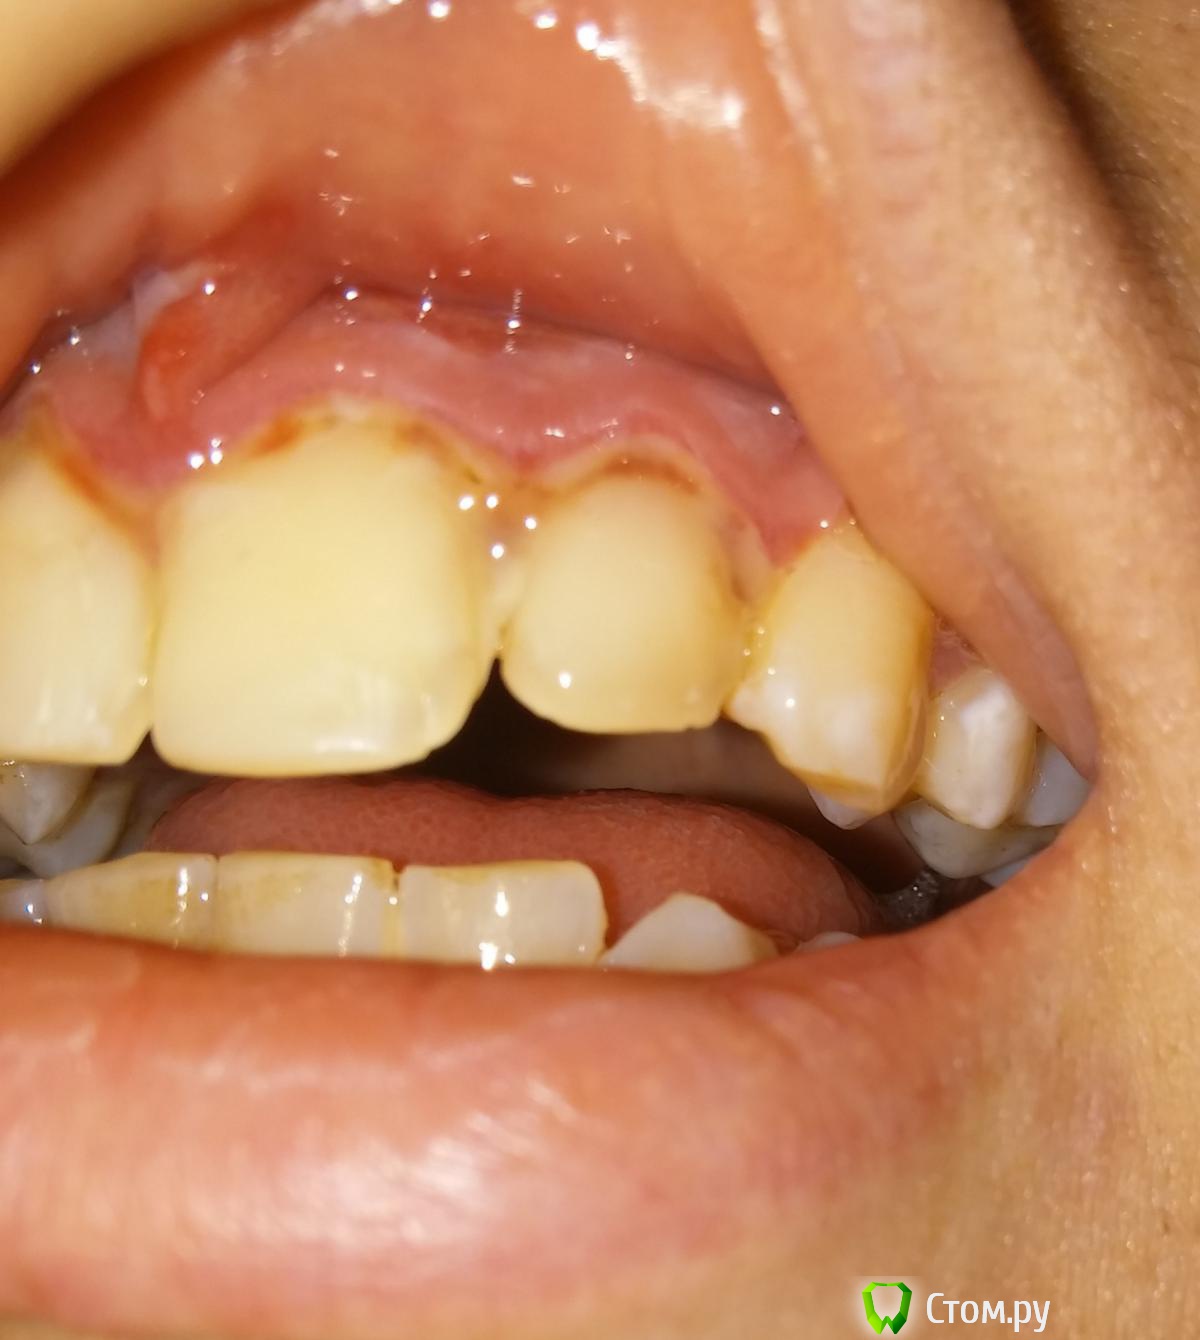

Виталий435 Опубликовано 23 августа, 2014 Поделиться Опубликовано 23 августа, 2014 Несколько лет назад мне запломбировали 4 передних верхних зуба около десны. В последнее время десна около этих 4 зубов воспалилась, врач сказал, что пломбы установлены плохо и упираются в десну. 3 дня назад мне переделали все пломбы, десна много кровила в процессе. Уже в конце процедуры десна была опухшей и опухлость так и не проходит. Это нормально? При начале лечения десна была воспалённой, но не опухшей. Также сейчас есть небольшая боль при движении верхней губой. Ссылка на комментарий

Виталий435 Опубликовано 23 августа, 2014 Автор Поделиться Опубликовано 23 августа, 2014 Вот. Только вспышка немного исказила цвет, зубы на самом деле выглядят белыми Ссылка на комментарий

red_butler Опубликовано 23 августа, 2014 Поделиться Опубликовано 23 августа, 2014 снимок конечно не ахти, но похоже проблема пародонтологическая. Сходите к пародонтологу Ссылка на комментарий

Виталий435 Опубликовано 23 августа, 2014 Автор Поделиться Опубликовано 23 августа, 2014 вполне, плюс делайте ванночки с 0,05 % хлоргекседином 3-4 р/д а вот эта белая плёнка на десне, это процесс заживления или воспаления? Ссылка на комментарий

red_butler Опубликовано 23 августа, 2014 Поделиться Опубликовано 23 августа, 2014 а вот эта белая плёнка на десне, это процесс заживления или воспаления?похоже на фибринозный налет, фибрин - элемент крови. Ссылка на комментарий

faity Опубликовано 23 августа, 2014 Поделиться Опубликовано 23 августа, 2014 (изменено) фибринозный налет в данном случае результат травмы, отек мягких тканей связан с ней же, нужно смотреть очно и ОПТГ сделатькогда ванночки будете делать хлоргексидиновые, не увлекайтесь, р-ор держать во рту по 15-20 сек Изменено 23 августа, 2014 пользователем faity Ссылка на комментарий